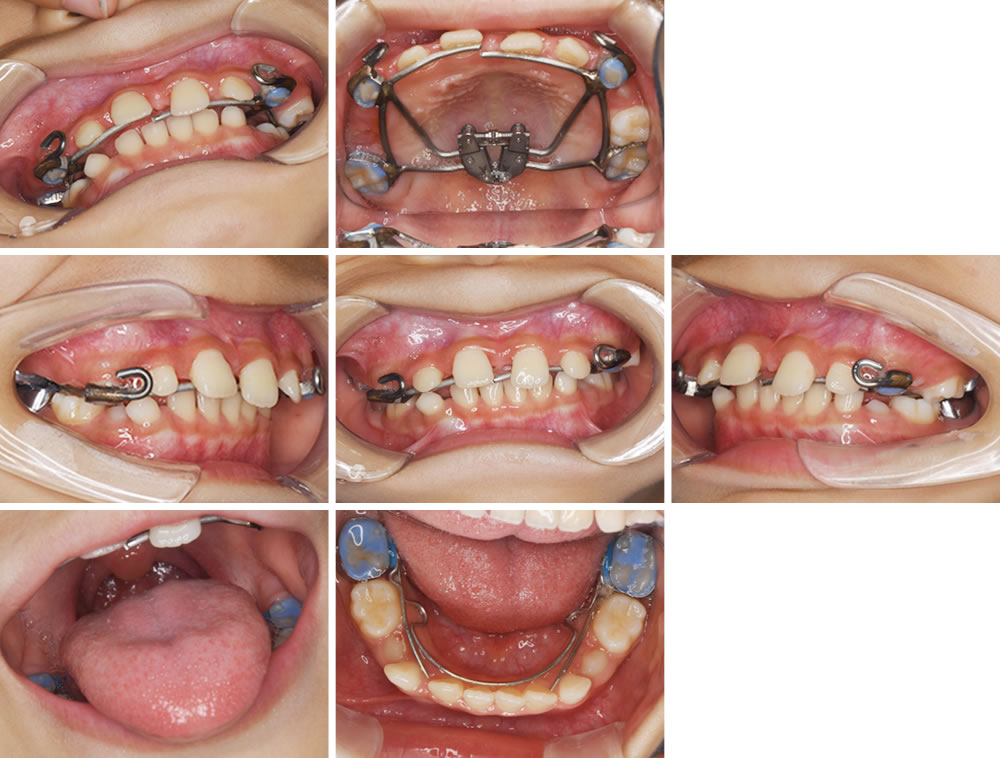

矯正治療途中の口腔内写真です。歯の生え変わりに合わせて、歯並びと骨格を調整していきます。